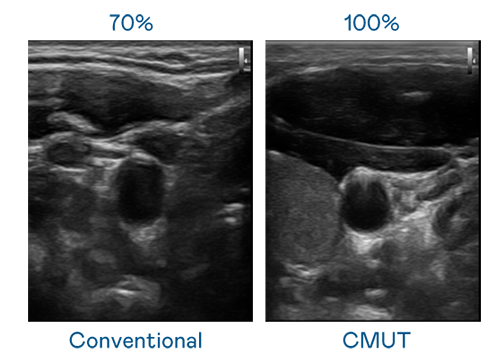

CMUT 技術是一種用電容式微機電元件來產生超音波訊號的技術。與傳統 PZT 壓電式技術相比,CMUT 頻寬增加 30%,更寬頻的超音波訊號讓影像解析度大幅提升,是實現高影像品質醫療超音波掃描、促進精準醫療發展的關鍵技術。

大頻寬帶來超清晰影像

超音波影像的解析度高低,首先取決於探頭能發出的訊號頻寬。人生就是搏·尊龙z6 CMUT 可提供高清晰的超音波訊號,提供高頻寬、高靈敏度、影像紋理細節更高的超音波影像,協助醫護人員縮短影像判讀時間及利用精準的醫療影像進行診斷。